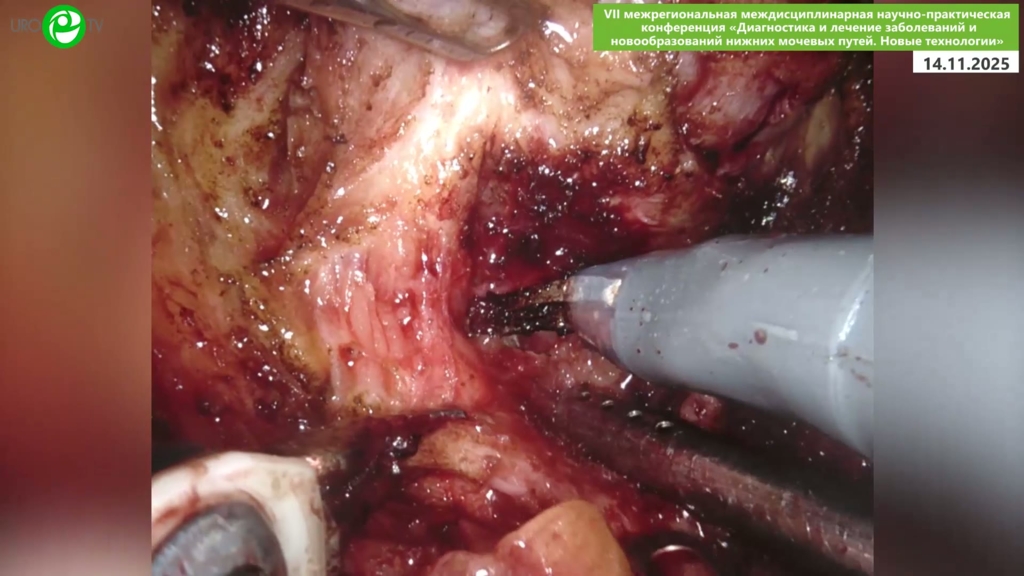

Безруков Е.А. - Робот-ассистированная простатэктомия с нервосбережением

20 ноя 2025